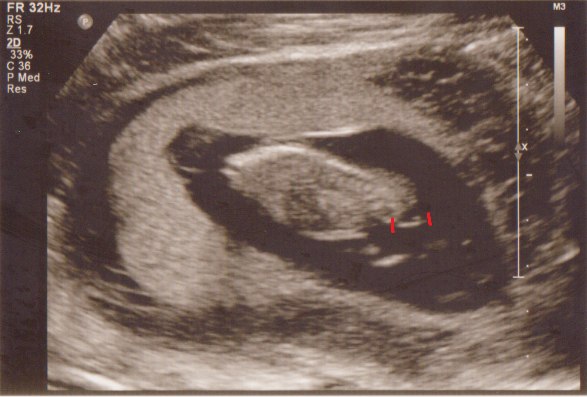

Vi fik med det samme øje på den lille guldklump som lå og hyggede sig gevaldigt inde i sin babyhule - h*n kunne slet ikke ligge stille, så det tog lidt tid inden hun fik målt nakkefolden, men i mellemtiden viste hun os hjernehalvdelene, mavesækken, næsebenet, alle 5 fingre på den ene hånd - kan næsten ikke huske alt det hun viste os - det var bare så fantastisk

Har lige prøvet at indikere det hun vurderede udfra